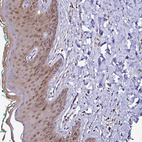

Immunohistochemistry analysis in human colon and skeletal muscle tissues using HPA047478 antibody. Corresponding TXN RNA-seq data are presented for the same tissues.